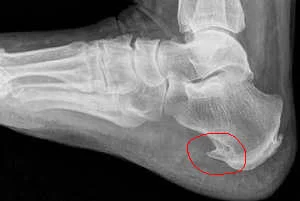

Обычно пяточная шпора хорошо видна на боковой рентгенограмме пяточной кости. На прямой проекции шпора полностью сливается с пяточной костью.

Шпора может иметь самую различную форму, чаще всего шиповидную или клиновидную, её основание сливается с бугром пяточной кости, а острие направлено вперёд (по ходу волокон подошвенного апоневроза), иногда в виде клюва несколько загнуто кверху. В некоторых случаях шпора имеет широкое основание и возвышается над массивом пяточной кости бугристым или шероховатым гребнем.

Шпора состоит из очень плотного бесструктурного вещества, которое сливается со склерозированными поверхностными слоями пяточной кости.